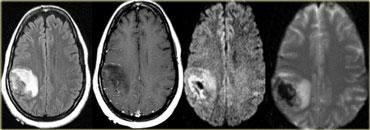

Trên chuỗi xung PD/T2W và FLAIR, nhồi máu não biểu hiện là vùng tăng tín hiệu.

Các chuỗi xung này phát hiện 80% nhồi máu não trước 24 giờ.

Chúng có thể âm tính trong vòng 2-4 giờ sau khởi phát!

Hình bên trái là chuỗi xung T2W và FLAIR cho thấy tăng tín hiệu trong vùng tưới máu của động mạch não giữa.

Lưu ý sự liên quan của nhân đậu và vỏ não đảo.

Tăng tín hiệu trên chuỗi xung MRI thông thường tương đương với giảm tỷ trọng trên CT.

Đây là kết quả của tổn thương không hồi phục với hoại tử tế bào.

Vì vậy, tăng tín hiệu có nghĩa là tiên lượng XẤU: não đã chết.

Hình ảnh Khuếch tán (DWI)

DWI là chuỗi xung nhạy cảm nhất trong chẩn đoán hình ảnh đột quỵ.